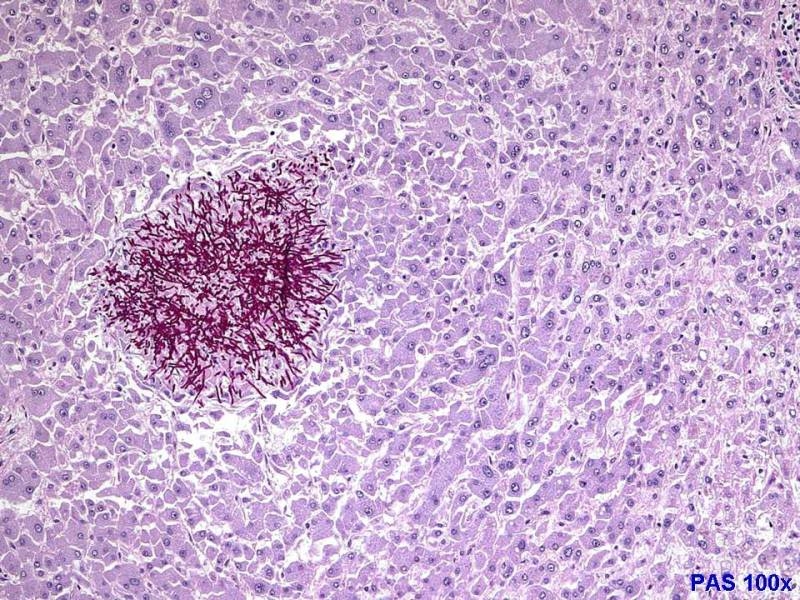

Mit die PAS Färbung wird Glykogen Rot/Purper angefärbt also könnte das eine Glykogenkrankheit sein??

Leberherd einer generalisierten Candidose ( Organcandidose ) bei Diabetes mellitus?

Genau - dies ist ein Leberherd bei einer Candida-Sepsis! Die Pilze haben sich bei dem Patienten über die Blutbahn im Körper verteilt und haben in den verschiedenen Organen Absiedlungen gebildet.

Tatsächlich kommt so etwas gelegentlich auch bei Diabetes mellitus vor.

meinst Du die sehr zirkumskripte herdförme Absiedlung ( ich hätte eventuell eher eine difuusere Ausbreitung erwartet ) ?

nun, der Patient ist nicht mehr am Leben, da haben sich die Pilze post mortem noch ein bisschen vermehrt. Aber eigentlich sind solche umschriebenen Kolonien recht typisch.

Nein, ich meine etwas anderes. Da werden Pilze im Körper verteilt. Das kommt schon mal vor, in der Regel aber ohne dass sich Absiedlungen in den Organen bilden. Warum? Und warum ist das hier trotzdem passiert?